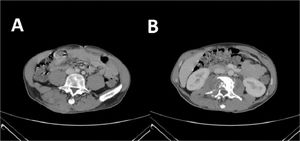

The patient was then admitted to the Infectious Diseases Unit and started treatment with MEM 2g three Times a Day (TID), amoxicillin/clavulanic acid 2.2g TID, LZD 600 mg two times a day intravenously (BID), and levofloxacin intravenously 500 mg BID. After one month of treatment, a CT scan showed a slight improvement of the abscess, but the bone injuries were unvaried (Fig. 2). We performed a second abscess sample showed a different resistance profile, now also showing resistance to meropenem. After approval by the hospital off-label drug committee, treatment with bedaquiline 400 mg daily for two weeks, followed by 200 mg three times per week, for 22 weeks, associated LZD 600 mg daily orally, RFB 450 mg daily, and amikacin 750 mg daily was started. Amikacin was discontinued after eight weeks. During treatment, a weekly Electrocardiogram (EKG) was performed. No QT prolongation was shown, but after 12 weeks of treatment, inverted T waves appeared; for this reason, several cardiological consultations and cardiac Magnetic Resonance Imaging were performed, but no cardiac dysfunction was found.

CT scan after the second treatment failure with Meropenem 2g three times a day, amoxicillin/clavulanic acid three times a day, linezolid 600 mg two times a day, and levofloxacin 500 mg two times a day. (A) presence of cutaneous abscess; (B) Presence of osteomyelitis on the second lumbar vertebra.